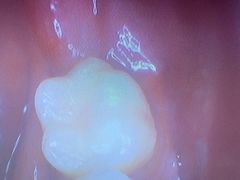

• 泰禾口腔医院

• -泰禾口腔医院

Cecile_6279 | 23-02-20